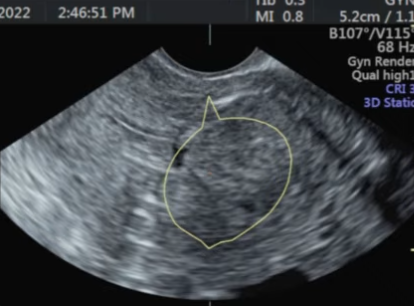

肌瘤类型和位置经评估适合做USgFUS。

MRI

USgFUS为子宫肌瘤患者提供了一种革命性的无创治疗选择,尤其适合有保宫需求、恢复时间要求高的女性。但它不是“万能神器”,其成功高度依赖于严格的术前影像评估和患者选择。